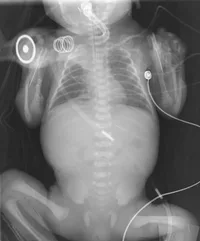

Señala la patologia